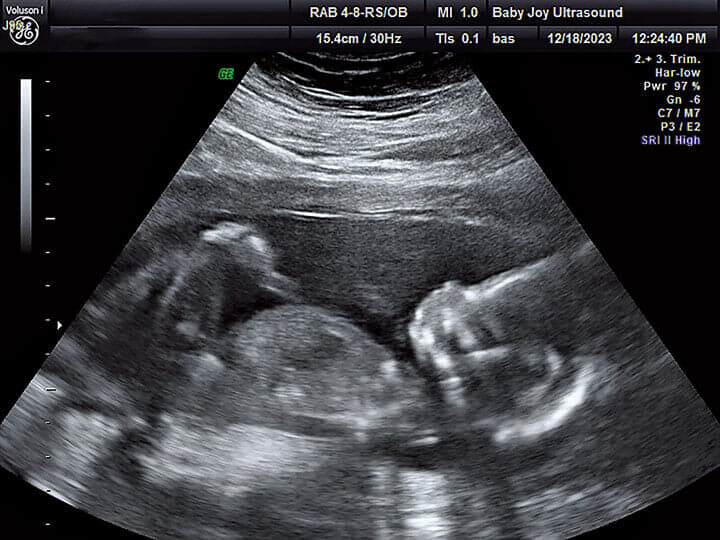

彼女の胎内ですくすく育つ赤ちゃんの超音波画像 VALERIE BAUMAN